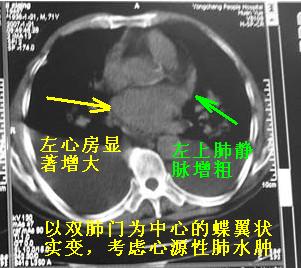

以下是引用陈维松c在2007-1-21 13:45:00的发言:[br]心衰肺水肿,胸腔积液。

以下是引用zyx168在2007-1-21 17:08:00的发言:[br]男,71岁,咳嗽、胸闷10天余,咯血1天。[br]两肺大片状密度均匀影,充气支气管征象明显,左房增大,双侧胸腔内新月形液性密度影。[br]考虑:1,心源性肺水肿伴双侧胸腔中等量积液;[br] 2,两肺肺炎?